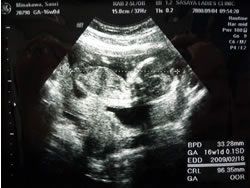

1ケ月ぶりに見るさおベビは 検診中も もぞもぞ ごにょごにょ 動いておりまして、元気いっぱい。

大きさも、158mmと、ついに3ケタいきまして、どんすこ 大きくなっていて 一安心。

超音波画像

映像を見て、あれ?って思った瞬間、先生から・・・

「名前はもう考えてるのかな? 性別言ったよね?」

って、聞いてないよーー!

サオリ「あ、聞いてないんですけど、 知りたいです」

「はい、   間違いなく    オトコノコですね」

というワケで、 あたしも気づいたくらいの、立派な証がついてたさおベビちゃんは、オトコノコなのです。